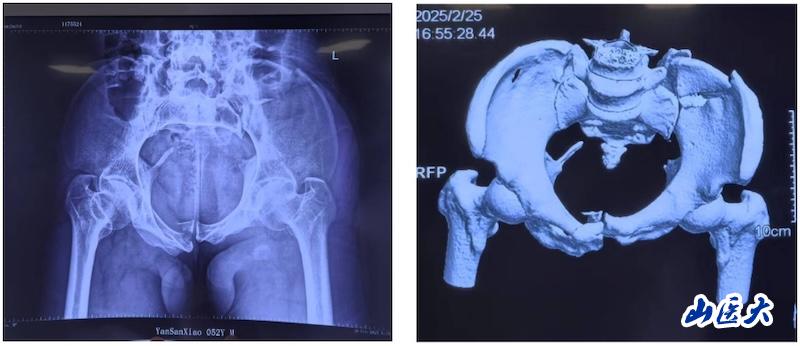

术前

该患者在驾驶三轮车时发生车祸,导致骨盆骨折,经过当地医院对症治疗后转入万象城第二医院急诊科。由于血色素持续下降,血管外科首先进行了血管介入栓塞处理,随后转入骨科创伤病区,由孙海钰团队接续治疗。经过详细检查和评估,孙海钰主任、贺冬冬副主任医师、王欢副主任医师为患者制定了运用UCRT解锁复位技术,结合天玑机器人及O-arm术中影像系统为其实施骨盆闭合复位的手术治疗方案。3月6日,孙海钰团队在骨科老一辈专家尹芸生主任的指导及麻醉师、技师、器械护士和巡回护士的通力协助下,成功运用微创新技术为患者实施了手术。